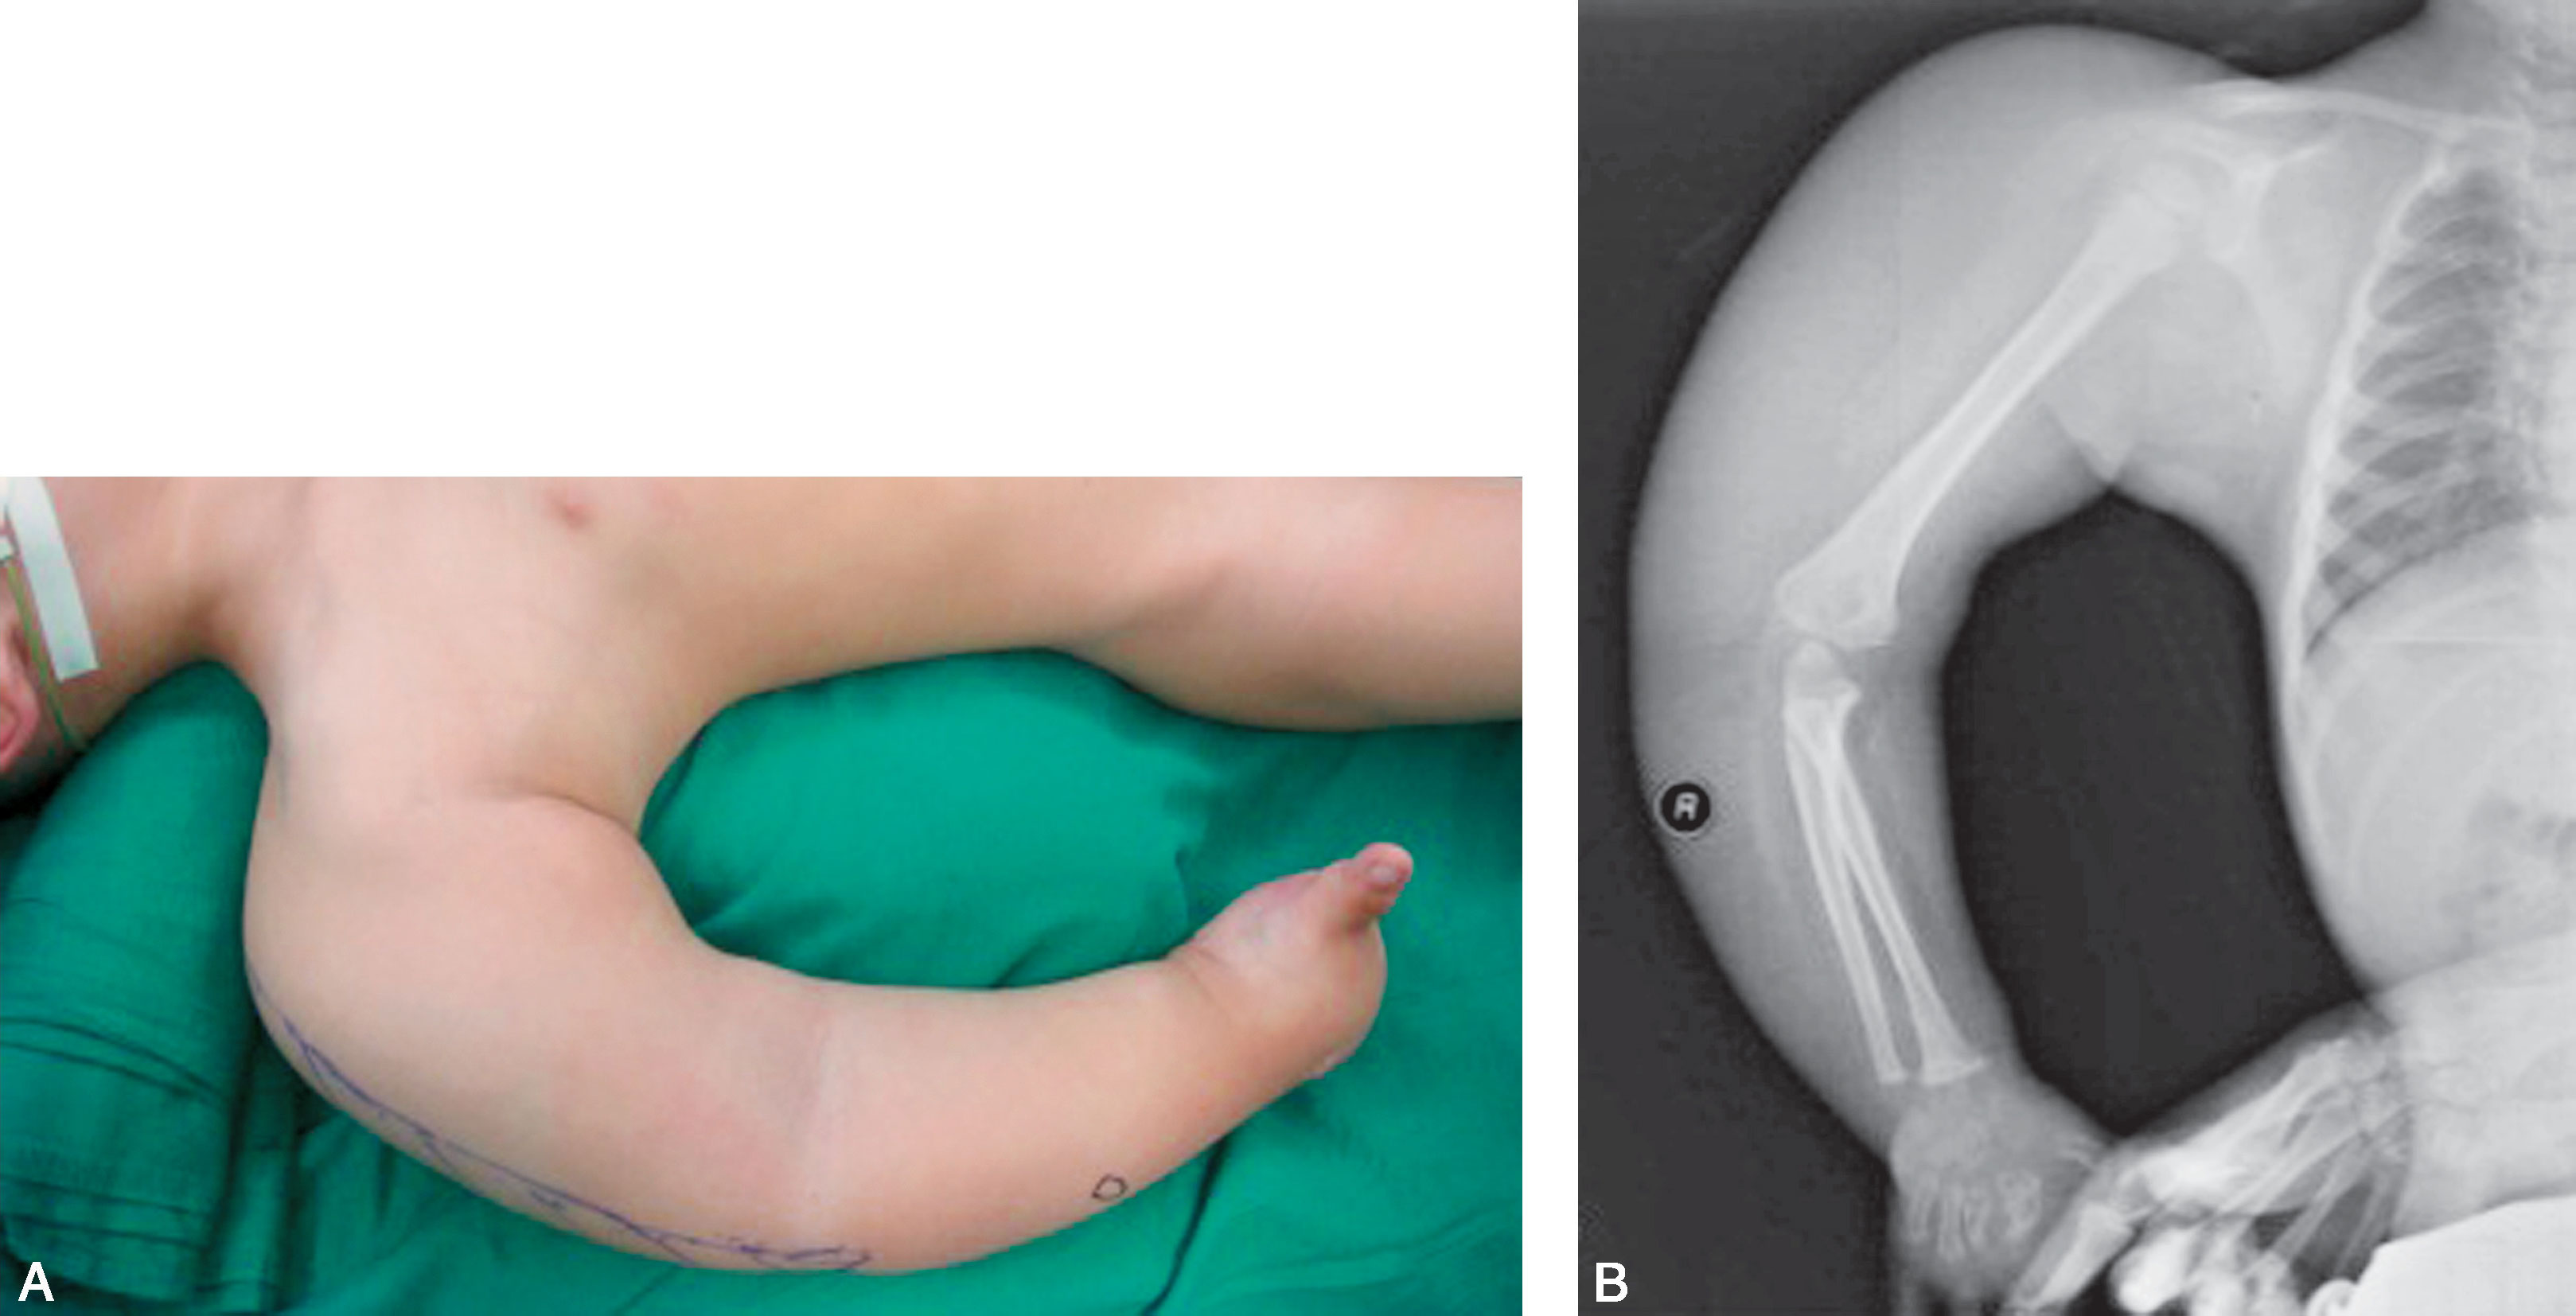

图1-2-21 全肘关节骨性融合病例

A.左侧前臂尺侧纵列发育不良;B.X 线片显示左侧肱骨桡尺骨融合(全肘关节融合),合并尺骨发育不良(尺骨远端部分缺如),桡骨继发性侧弯,第Ⅰ、Ⅱ及第Ⅳ、Ⅴ掌骨融合